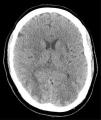

Presentamos el caso de un varón de 41 años, sin antecedentes de interés salvo hernia de hiato con reflujo gastroesofágico y esófago de Barret, ingresado en la UCI en el postoperatorio de reducción de hernia de hiato y funduplicatura de Nissen vía laparoscópica, complicado con perforación gástrica y con fracaso multiorgánico con componente respiratorio, renal y hemodinámico, del que se había recuperado con tratamiento de soporte (ventilación mecánica, fármacos vasoactivos y hemodiafiltración venovenosa continua). Durante la fase de recuperación, una vez extubado y con depuración extrarrenal intermitente (hemodiálisis lenta continua a demanda en función de creatinina, iones y volemia) desarrolla una hipertensión arterial (HTA) moderada con tensión arterial sistólica (TAS) máxima de 170mmHg y diastólica (TAD) de 95mmHg (aunque estos valores eran puntuales y estaba manteniendo tensiones medias de alrededor de 95-100mmHg) que se trata con antihipertensivos con escasa respuesta. De forma súbita desarrolla ceguera cortical. Se realiza tomografía axial computarizada (TAC) y resonancia magnética nuclear (RMN) de cráneo. En la TAC se describe hipoatenuación córtico-subcortical bioccipital y biparietal baja, con pérdida de la diferenciación sustancia gris-sustancia blanca. En la RMN se observan múltiples lesiones hiperintensas en T2 y FLAIR afectando a la sustancia blanca subcortical, de forma difusa en la convexidad, y más discretamente la cortical con mayor afectación de la región parietooccipital bilateral (donde además está afectando a la cortical del forma más severa), y discreta afectación temporal bilateral. Hay también lesiones en el esplenio del cuerpo calloso, y en ganglios basales y bilaterales. Las lesiones tienen un comportamiento bilateral y simétrico. Hay restricción de la difusión de lesiones córtico-subcorticales parietooccipitales bilaterales de predominio derecho. Estas lesiones son compatibles con el síndrome de encefalopatía posterior reversible (figs. 1 y 2).

La afectación radiológica es característica, objetivándose en la RMN una señal hiperintensa en T2 y FLAIR que afecta de forma simétrica a la sustancia blanca subcortical, sobre todo a nivel posterior, que no resalta con contraste ni presenta alteración significativa de la difusión, compatible con edema vasogénico. No hay alteración en la vasculatura salvo vasoespasmo en un 4%. La distribución es parieto-occipital (94%), frontal (77%), temporal (64%), cerebelosa (58%), ganglios de la base (34%) y tronco (27%). Estas lesiones son reversibles en días o semanas si no se complican con hemorragia (15% de los casos) e infarto. A veces tiene presentaciones más atípicas siendo asimétricas, afectando a córtex (10%), con captación de contraste típicamente a nivel giriforme o ocasionando restricción a la difusión (20%)3. Estas últimas lesiones se han asociado a un mal pronóstico4.